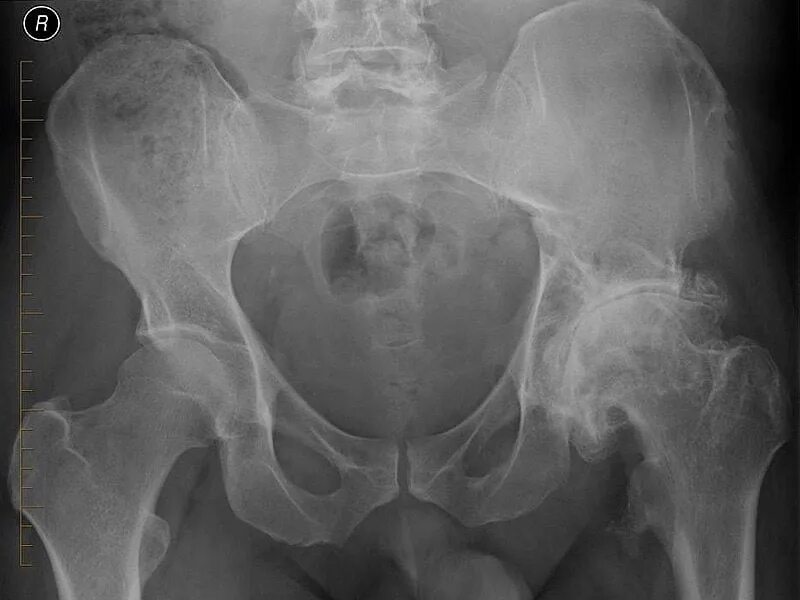

4 стадия тазобедренного сустава